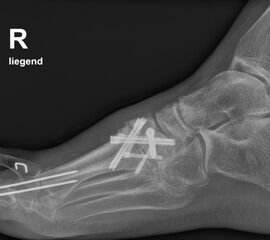

• konventionelle Röntgenbilder mit Belastung im Stehen a. p. und seitlich, ggf. schräg (Abb. 9, 10 und 11).

• Röntgenkontrolle nach 8-10 Wochen, dann - je nach knöchernem Durchbau - Übergang zur Vollbelastung im Konfektionsschuh (Abb. 24 und 25).